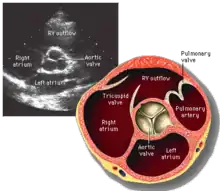

Vue à axe court de la valve aortique du cœur accompagné d'une échographie.

Le dysfonctionnement de la valve aortique est de deux ordres principaux. Le rétrécissement aortique désigne une ouverture incomplète de la valve qui est remaniée pendant la Systole. Ceci a pour conséquence une résistance trop importante au passage du sang du ventricule gauche vers l'aorte, ce qui entraîne une hypertrophie du ventricule gauche. L'insuffisance aortique désigne une anomalie caractérisée par la présence d'un reflux de sang de l'aorte vers le ventricule gauche au cours de la Diastole, ce qui entraîne une dilatation du ventricule gauche.

L'échocardiographie permet de visualiser la valve aortique, d'étudier sa morphologie et son fonctionnement.